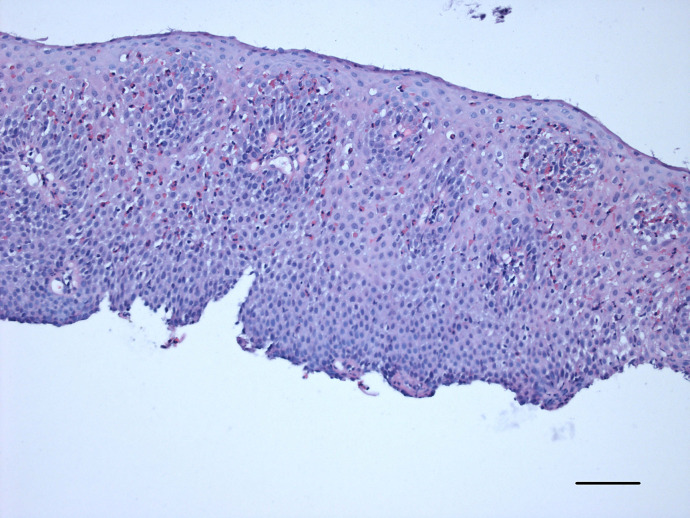

Background: Eosinophilic esophagitis is an increasing condition in industrialized countries. The etiology is still somewhat unclear. It was thought that it can be part of eosinophilic gastroenteritis but nowadays seen as a separate entity and thus more often the esophagus is the only part of the gastrointestinal tract that is affected. Immunosuppressive and immunomodulatory treatment is available and can lead to symptom relief and remission.

Summary and key messages: In this article, the value and practicability of the histological criteria used for this disease are discussed. Also, the situation regarding the requirements for grading in clinical studies and routine settings is discussed.